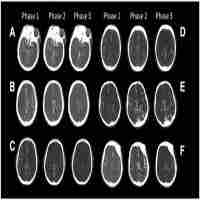

| Abstract | The presence of a native collateral circulation in tissues lessens injury in occlusive vascular diseases. However, differences in genetic background cause wide variation in collateral number and diameter in mice, resulting in large variation in protection. Indirect estimates of collateral perfusion suggest that wide variation also exists in humans. Unfortunately, methods used to obtain these estimates are invasive and not widely available. We sought to determine whether differences in genetic background in mice result in variation in branch patterning of the retinal arterial circulation, and whether these differences predict strain-dependent differences in pial collateral extent and severity of ischemic stroke. Retinal patterning metrics, collateral extent, and infarct volume were obtained for 10 strains known to differ widely in collateral extent. Multivariate regression was conducted, and model performance was assessed using K-fold cross-validation. Twenty-one metrics varied with strain (p < 0.01). Ten metrics (e.g., bifurcation angle, lacunarity, optimality) predicted collateral number and diameter across seven regression models, with the best model closely predicting (p < 0.0001) number (±1.2–3.4 collaterals, K-fold R 2 = 0.83–0.98), diameter (±1.2–1.9 μm, R 2 = 0.73–0.88), and infarct volume (±5.1 mm3, R 2 = 0.85–0.87). An analogous set of the most predictive metrics, obtained for the middle cerebral artery (MCA) tree in a subset of the above strains, also predicted (p < 0.0001) collateral number (±3.3 collaterals, K-fold R 2 = 0.78) and diameter (±1.6 μm, R2 = 0.86). Thus, differences in arterial branch patterning in the retina and the MCA trees are specified by genetic background and predict variation in collateral extent and stroke severity. If also true in human, and since genetic variation in cerebral collaterals extends to other tissues at least in mice, a similar “retinal predictor index” could serve as a non- or minimally invasive biomarker for collateral extent in brain and other tissues. This could aid prediction of severity of tissue injury in the event of an occlusive event or development of obstructive disease and in patient stratification for treatment options and clinical studies. |